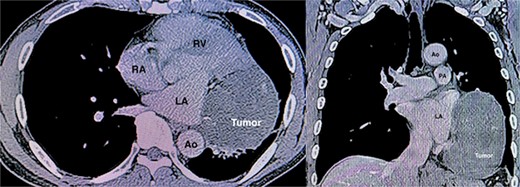

A 57-year-old male patient presented with dyspnea. His medical history, physical examination, and laboratory tests were unremarkable. The electrocardiogram revealed regular sinus rhythm without ST changes. A chest X-ray detected an abnormal shadow in the right lung hilum. Transthoracic echocardiography (TTE) revealed an extracardiac mass with a halo measuring 5.5 × 7.5 cm attached to the left atrial posterior wall. Contrast-enhanced computed tomography (CT) revealed a heterogeneously enhancing 8.9 × 7.3 × 12.2 cm mediastinal mass with peripheral calcifications silhouetting the left cardiac border with fat plane separation (Fig. 1). The exact kind of the tumor, including whether benign or malignant, was unknown preoperatively. We planned to remove the tumor both for diagnostic purposes and treatment. We didn’t perform a preoperative pathological diagnosis in this case due to the risks of cardiac injury and bleeding. Surgical resection via left thoracotomy was performed, as the patient expressed a desire for an early return to daily life and work, as this approach avoids a median sternotomy and reduces the risk of complications, such as mediastinitis.

CT angiography demonstrating a huge tumor (8.9 × 7.3 × 12.2 cm) measuring adjacent to the left atrium (LA) and left ventricle (LV). Ao, ascending aorta; RA, right atrium; RV, right ventricle; PA, pulmonary artery.